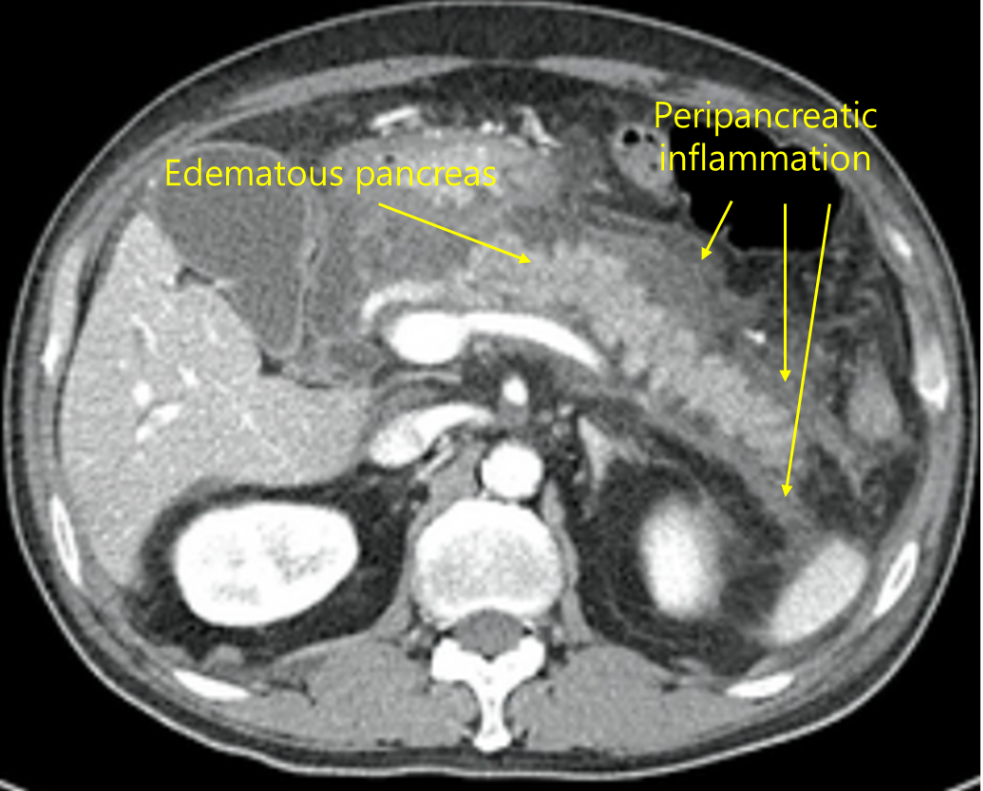

46세 남자가 2일 전부터 윗배가 아프다고 병원에 왔다. 메스꺼움도 심하고 구토를 여러 차례 했다. 5년간 거의 매일 소주 2병씩을 마셨다고 한다. 혈압 100/70mmHg, 맥박 100회/분, 호흡 20회/분, 체온 36.9℃이다. 복부 청진에서 장음은 감소되어 있었다. 배꼽 주변 윗배에 압통이 있으나 반동압통은 없다. 혈액 검사 결과는 다음과 같다. 복부 컴퓨터단층촬영 사진이다. 치료는?

아스파르테이트아미노전달효소 258U/L, 알라닌아미노전달효소 139U/L, 알칼리인산분해효소 348U/L, 아밀라아제 610U/L, 리파아제 860U/L

Img | CT: 췌장 종대 및 췌장 주위 fluid collection |

급성 상복부 통증, 오심, 구토, 심한 음주력, 혈액검사 상 amylase, lipase의 상승, 복부 CT 상 췌장 주위의 fluid collection으로부터 급성 췌장염을 진단할 수 있다. 급성 췌장염의 치료는 수액 공급, 진통제 등 보존적 치료가 우선이다.

진단 | • US: 담석, 담관확장 확인 • CT: 췌장 실질의 edema, 췌장 근처 조직의 inflammation |